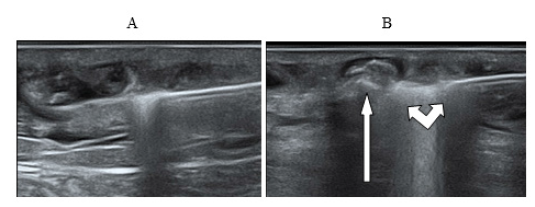

The process of ultrasonic navigation, during the ELTA procedure, is directly related to the control of the boiling zone of blood at the end of the light guide with the formation of a hyperechoic vapor-gas mass in the lumen of the vessel and compression of the venous wall. Figure 4 shows ultrasound images of various stages of laser coagulation using various light guides with the effect of bubble formation and assessment of blood flow in Doppler mode.

Figure 4:(A) The light guide in the lumen of the vein; (B) Ultrasound picture of the generation of the first bubble during thermocoagulation using laser radiation with a wavelength 1.47 microns and power 7.5 watts.

Ultrasound observation in Doppler mode allows us to record a slowdown in blood flow from the main vein to the surface inflow sometime after the start of the procedure. Later on, the blood flow stops completely. During the procedure, one can observe an active movement of a vapor-gas substrate (foam) in the lumen of the main vein, which spreads through the lumen of the ablated vein and fills the “knee bends” - the convoluted parts of the vessel with varicose extensions [9].

During the boiling process, the blood foams, spreading along the vein and forming a foamy occlusion of the vessel [9]. The “life time” of the foam is less than 24 hours, because on the next day, during a control study in the lumen of ablated veins, the presence of a hyperechoic substrate with gas inclusions is already not detected. A day after the skewer ablation procedure, the vein becomes ablated: the lumen of the vessel is filled with heterogeneous detritus, the walls of the vein are not thickened, there is no blood flow, perivascular tissues have no signs of compaction/inflammation.